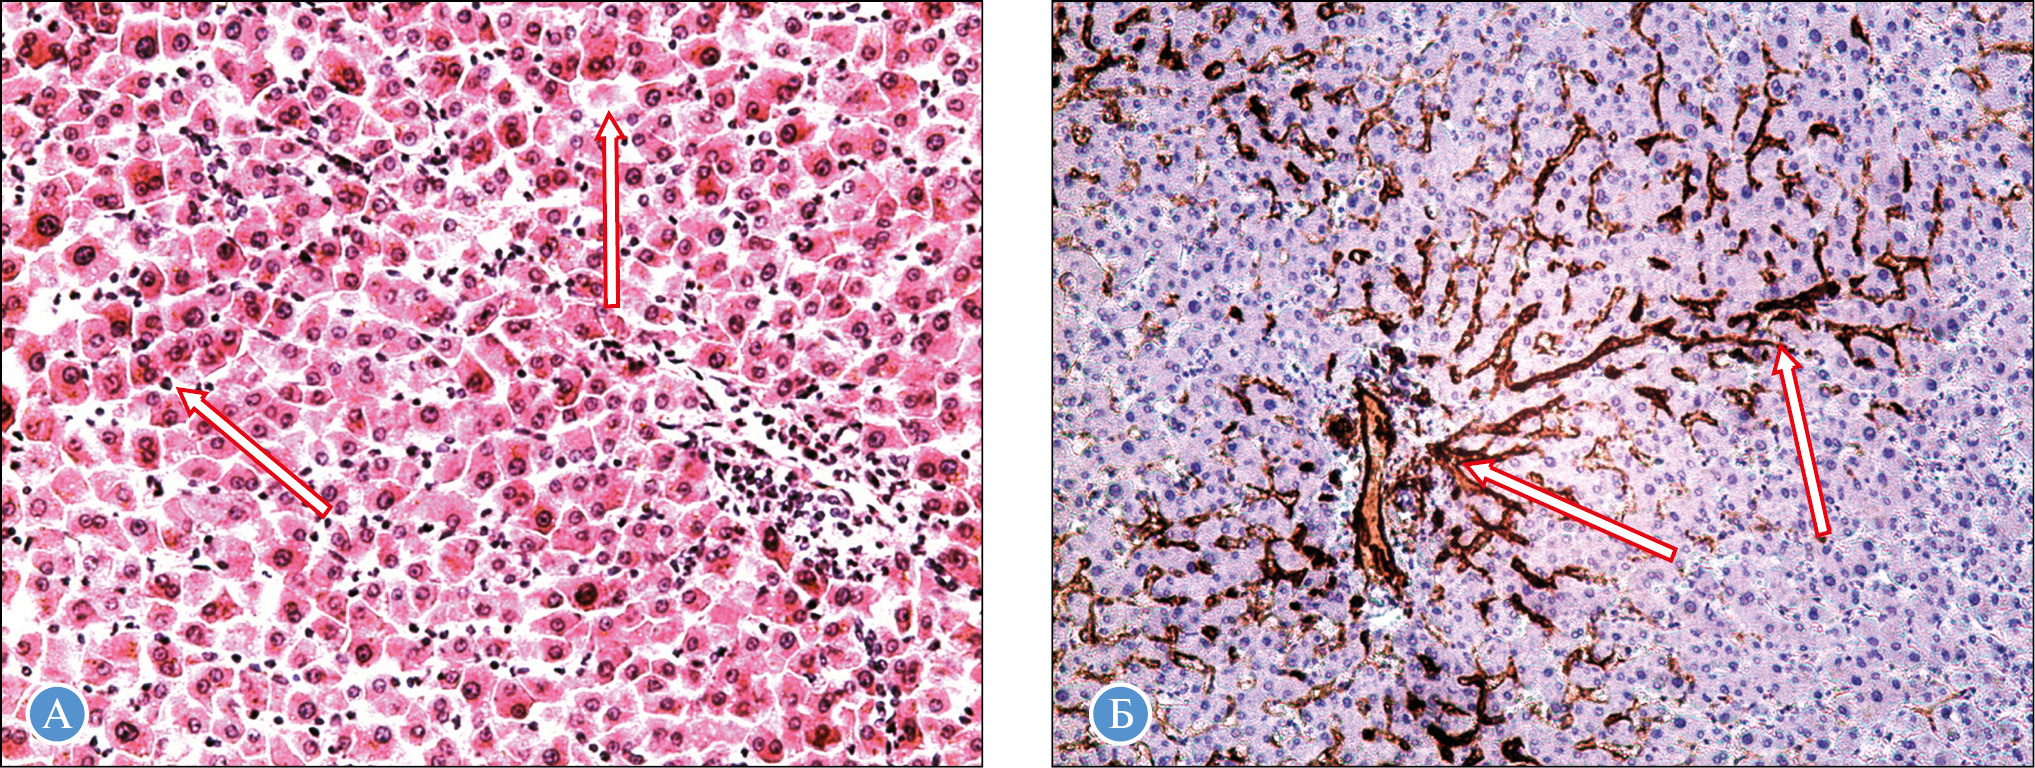

Патоморфология печени в группе сравнения. Беременность сопровождается существенной нагрузкой на печень. Так, в группе сравнения в микропрепаратах видна явная гипертрофия гепатоцитов в виде крупных ядер и двуядерных форм. Эти изменения сконцентрированы в перипортальной зоне (зона 1) печеночного ацинуса, где имеют место лучшие условия для кровоснабжения (рис. 1, А). Это подтверждается маркером CD-34, который четко контурирует сеть капилляров-синусоидов в зонах 1 и 2 ацинуса (рис. 1, Б) и практически отсутствует в перивенулярной зоне. Этим обусловлены преобладающие дистрофические изменения в гепатоцитах вокруг центральной вены вследствие снижения перфузии (как артериального, так и венозного кровотока). Наблюдаются также повреждение микроциркуляторного русла, очаговый некроз гепатоцитов, что характерно для острой циркуляторной недостаточности и разных видов шока, регистрируемых у женщин из группы сравнения.

Рис. 1. Группа сравнения: А — наличие гипертрофированных двуядерных гепатоцитов (стрелки) в перипортальной области (зона 1 ацинуса) (патоморфологическое исследование, окраска гематоксилином и эозином, ×100); Б — разветвленная капиллярная сеть (стрелки) в зоне 1 и отчасти в зоне 2 ацинусов (иммуногистохимическое исследование с маркером CD-34, ×50)